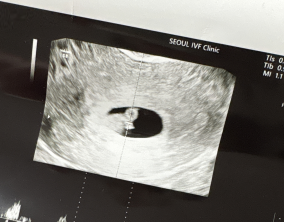

설렘과 불안의 시간을 지나 찾아온 선물

서울IVF여성의원의 난임 치료는 과정 하나하나가 체계적이고 세심하다는 인상을 받았습니다. 이유정 원장님과 간호사 분들께 치료 단계마다 충분한 설명을 들을 수 있어 불안이 많…